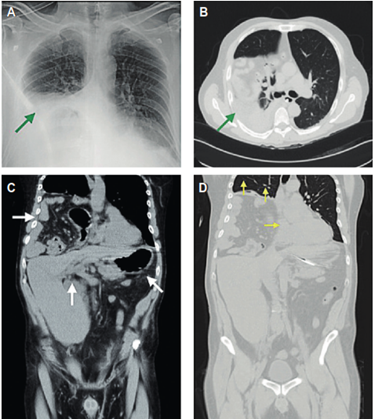

Presentamos el caso de un paciente de 51 años que acude al servicio de Urgencias por disnea y dolor torácico persistente. El paciente reportó también sensación de náusea, disfagia, hiporexia, dolor abdominal moderado y ausencia de evacuaciones en 72 horas. La exploración inicial reveló 20 respiraciones por minuto, saturación de oxígeno 96%, y no se documentó fiebre, a pesar de cursar con síntomas de enfermedad grave. La radiografía de tórax evidenció zona de opacidad basal derecha. La prueba de antígeno y PCR resultaron positivas para COVID-19. Se realizó una tomografía tóraco- abdominal la cual demostró la presencia de hernia hiatal mixta y vólvulo gástrico; en el parénquima pulmonar no se observaron cambios sugestivos de neumonía por SARS-CoV-2 (Figura 1).

Figura 1: A) Radiografía posteroanterior con opacidad en hemitórax derecho. B) Tomografía de tórax en plano axial que revela estómago, intestino delgado, colon y mesenterio en situación intratorácica derecha; no se observan cambios en parénquima pulmonar compatibles con neumonía viral. C) Tomografía tóraco-abdominal (plano coronal) que demuestra hernia hiatal con hemidiafragma derecho de situación alta y vólvulo gástrico. D) Tomografía en plano coronal que muestra restricción mecánica del pulmón derecho con desplazamiento contralateral de estructuras mediastinales. Imagen original, fuente: los autores.

La discordancia entre el cuadro clínico, la exploración física y los hallazgos radiográficos iniciales, puede ser objeto de confusión en una enfermedad emergente y multisistémica2. Los hallazgos por tomografía de tórax han demostrado una buena correlación con la severidad de la enfermedad3. En este caso, los síntomas (incluyendo la disnea y dolor torácico) fueron secundarios a la restricción mecánica del parénquima pulmonar, probablemente en un paciente con enfermedad COVID-19 leve o asintomática.